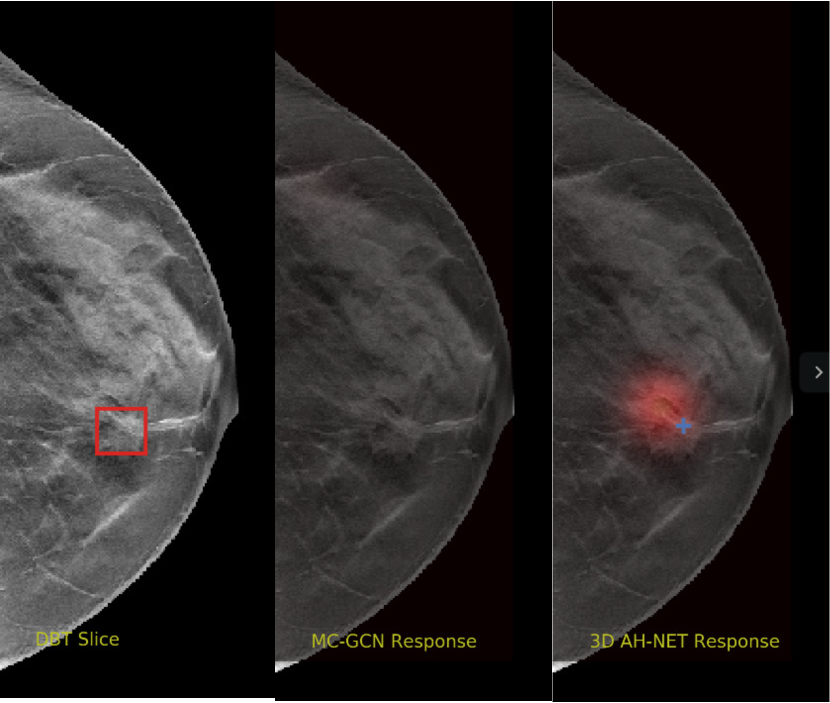

We selected some example slices from the DBT dataset to demonstrate the advantage of our proposed AH-Net for the Breast cancer screening. From Fig. 8 to Fig. 12, we show slices from five test DBT volumes that both the MC-GCN and the proposed 3D AH-Net could successfully detect the suspected breast lesion. The original DBT slice is shown on the left with the lesion annotated by our radiologist. Please note the original annotation is a 3D box. The figures in the middle and on the right are response maps from MC-GCN and 3D AH-Net overlaid on the original image, respectively. The detection locations obtained with non-maximal suppression are displayed with cross markers. As shown in the images, the proposed network can detect breast lesions varying in sizes and appearances. The confidence of the 3D AH-Net is usually higher than that of MC-GCN. From Fig. 13 to Fig. 17, we show five volumes that MC-GCN failed to detect the lesions since the lesions were not distinguishable from other breast tissues using the information within the slice. In contrast, 3D AH-Net was able to detect the lesions from such volumes using the 3D context between slices. As shown in Fig. 18 to Fig. 22, there are also volumes with lesions that both network failed to detect. Such lesions normally reside in the dense breast tissues. The boundary between these lesions and the normal breast tissues usually have low contrast. The networks sometimes also confuse them with other roundish structures in the breast such as lymph nodes or skin moles.

Figure 13: Example DBT slice 6 with a lesion that can only be detected by 3D AH-Net. The lesion is highly blended within the dense breast tissues which makes it challenging for both the radiologists and the networks to detect through a single slice. In contrast, the lesion can be detected by considering the consistency of the structure across a few neighbouring slices.

Refer to caption